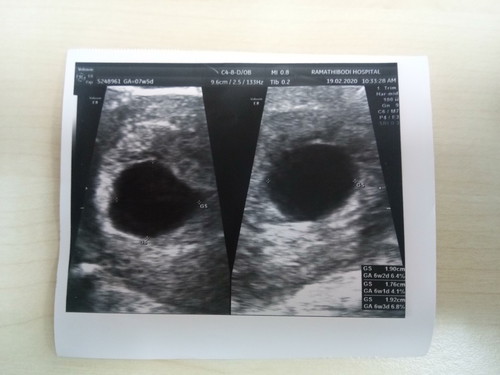

เมื่อวันที่19/2/63ไปฝากครรภ์ +ฟังผลเลือด อายุครรภ์ประมาณ7W 3D หมอเเจ้งเจอเเต่ถุงตั้งครรภ์เเต่ไม่เจอน้อง อย่างน้อยเเม่ก็โล่งใจไป1 ด่าน เพราะถุงตั้งครรภ์มาในมดลูก เเต่หมอเเจ้งว่าขนาดถุงใหญ่กว่าปกติ เเต่ไม่พบน้อง อาจเป็นไปได้2อย่าง คือ1น้องยังเล็ก กับ2อาจเสี่ยงท้องลม เเต่ช่วงนี้เเม่ไม่มีอาการเเพ้เเต่อย่างใดเลย น้องจากนอนเก่ง เจ็บหน้าอกบ้างบางครั้ง เริ่มมีเบื่ออาหารบ้าง เเต่ไม่อ้วกนะคะ อยากถามเเม่ว่าอาการของท้องลมเป็นเเบบใหนกันบ้างค่ะ

เป็นเหมือนกันค่ะแม่ ตอน7w ซาวไม่เจอน้องแต่ถุงตั้งครรภ์ใหญ่ขึ้น แม่แอบกังวลเหมือนกัน วันนี้ 12w2D เจอหัวใจน้องแล้ว มีครบค่ะ (รูปไม่ค่อยชัดนะคะ) แม่อย่าคิดมากนะคะ